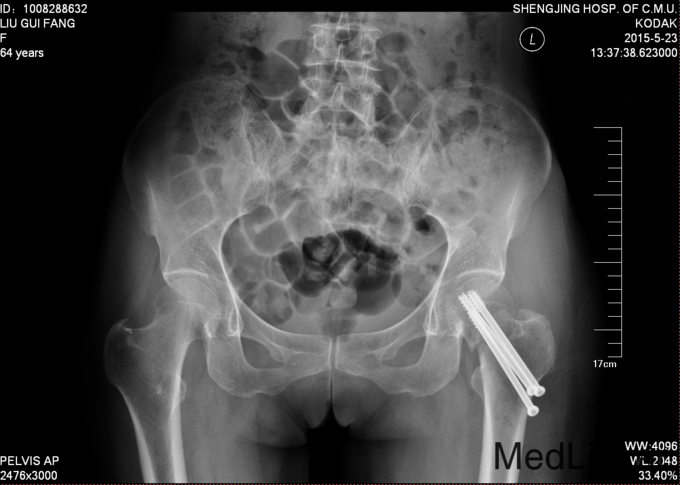

患者,女,64岁,自述2015-5-14日11:30于家附近骑自行车不慎摔伤,伤后意识清晰,左下肢疼痛肿胀活动受限,患者将其急送往辽中县县医院,急诊予以行辅助检查,提示:左股骨颈骨折。 后转至我院急诊。现患者为求进一步诊治,以“左股骨颈骨折”为诊断收入我科。病来患者一般状态 可,意识清晰,饮食可,睡眠可,二便正常。

患者平车推入病房,左下肢可见外旋畸形,患者被动体位,下肢短缩0.5cm。左下肢疼痛肿胀活动受限,足趾背伸跖屈肌力5级,足背部及小腿感觉无麻木。足背动脉可触及搏动。其余肢体未见异常。。

诊断:左股骨颈骨折 患者入院后完善检查,诊断为股骨颈骨折,考虑患者一般状态好,年龄在65岁以下,所以查无手术禁忌症后行左股骨颈骨折闭合复位内固定术。术后第二天,患者自动退院。

患者年龄为65岁以下,主张行空心钉治疗,经皮空心钉治疗微创手术,在牵引床的帮助下,复位一般情况良好。